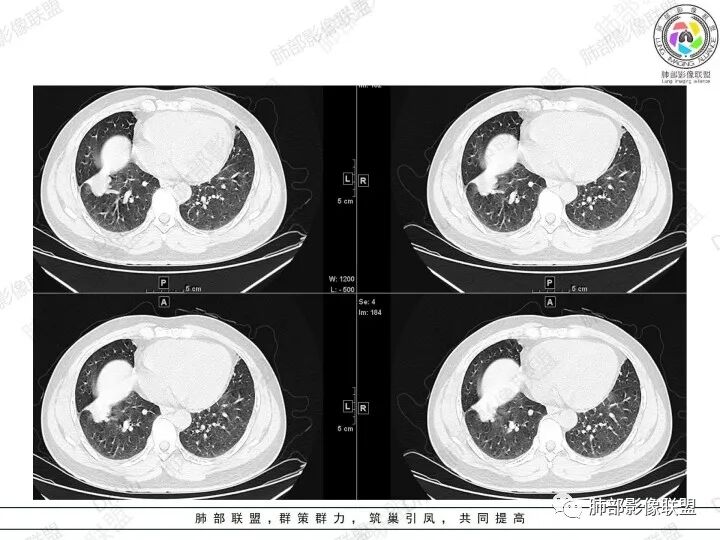

2、胸部CT右肺下叶胸膜下肿块性病变,边缘可见分叶毛刺、边缘膨隆,似有指状凸起,邻近胸膜稍牵拉凹陷,叶间裂以为不明显,提示收缩力较弱。近端支气管进入后截断,病灶内密度尚均匀,增强后可见轻度强化,未见空洞或钙化,并可见血管影进入。右侧肺门及纵隔内可见肿大淋巴结影。无胸腔积液。

3、综合患者临床症状及影像表现,需要考虑肿瘤性病变和非肿瘤性病变,肿瘤性病变需要考虑普通浸润性腺癌或结节型粘液腺癌、淋巴瘤、淋巴上皮瘤样癌、小细胞肺癌等,非肿瘤性病变主要考虑肺脑同病中的隐球菌。①普通浸润性腺癌,以肺外周多年、混合磨玻璃或实性结节/肿块,多见分叶、毛刺、胸膜凹陷、血管集束等征象,本例收缩力较弱、且强化偏轻,不够典型。②粘液腺癌,腺癌的特殊类型。多位于胸膜下(90%位于胸膜下,70%位于下叶胸膜下),边缘清或不清的GGO:提示粘液外渗,少数为纯GGO,缺乏中心纤维化区:毛刺、胸膜凹陷征少,很少胸膜侵犯,淋巴结转移少见,增强后无强化或低强化,本例病灶位于胸膜下,强化轻,收缩力弱,结节期粘液腺癌确实可以符合。③小细胞肺癌,吸烟男性多见,典型征象包括娘小崽大、腊肠样凸起、冰冻纵膈等,本例胸膜下病变大、但肺门淋巴结肿大程度较轻,不符合常见小细胞癌生物学行为,但有可疑指状凸起,小细胞肺癌不能完全除外。④淋巴上皮瘤样癌,少见的恶性肿瘤,患病年龄较轻,肿瘤多位于胸膜下,边缘多光滑,病灶周围可见磨玻璃,毛刺及分叶、胸膜凹陷少见,近端支气管可截断,增强多为中度-明显强化,本例除了强化程度偏轻外,影像表现基本可符合。⑤淋巴瘤,原发肺内淋巴瘤较少见,病灶多位于支气管血管束周围或胸膜下,密度多较均匀,边缘可膨隆也可平直收缩,可见支气管充气征、血管造影征等,强化多为轻中度,本例肺内结节血管穿行自然,局部有血管漂浮,长轴与支气管走行基本一致,肺门淋巴结肿大,不能排除。⑥隐球菌,影像表现可分为孤立结节型、大片实变型、多发结节或实变型、弥漫型。病变多位于胸膜下,边缘平直为主、可伴晕征,可见支气管穿行、部分可见支气管截断,密度多较均匀,部分可伴空洞,增强多为轻中度强化、延迟强化。本例病变位于胸膜下,收缩力弱,强化程度轻,但没有呼吸道症状,病变近端支气管截断,肺门淋巴结大,这些征象都难以用隐球菌解释,基本排除。

总之,本例考虑到恶性肿瘤性病变多不困难,但诊断到粘液性癌并不容易。

结节型粘液腺癌的影像诊断:

1.位于胸膜下(90%位于胸膜下,70%位于下叶胸膜下)

2.边缘清或不清的GGO:提示粘液外渗,少数为纯GGO

3.缺乏中心纤维化区:毛刺、胸膜凹陷征少,很少胸膜侵犯率

4.淋巴结转移少见

5.增强后无强化或低强化

6.典型征象:圆圈征、草帽征、树上蘑菇征、GGO样卫星灶